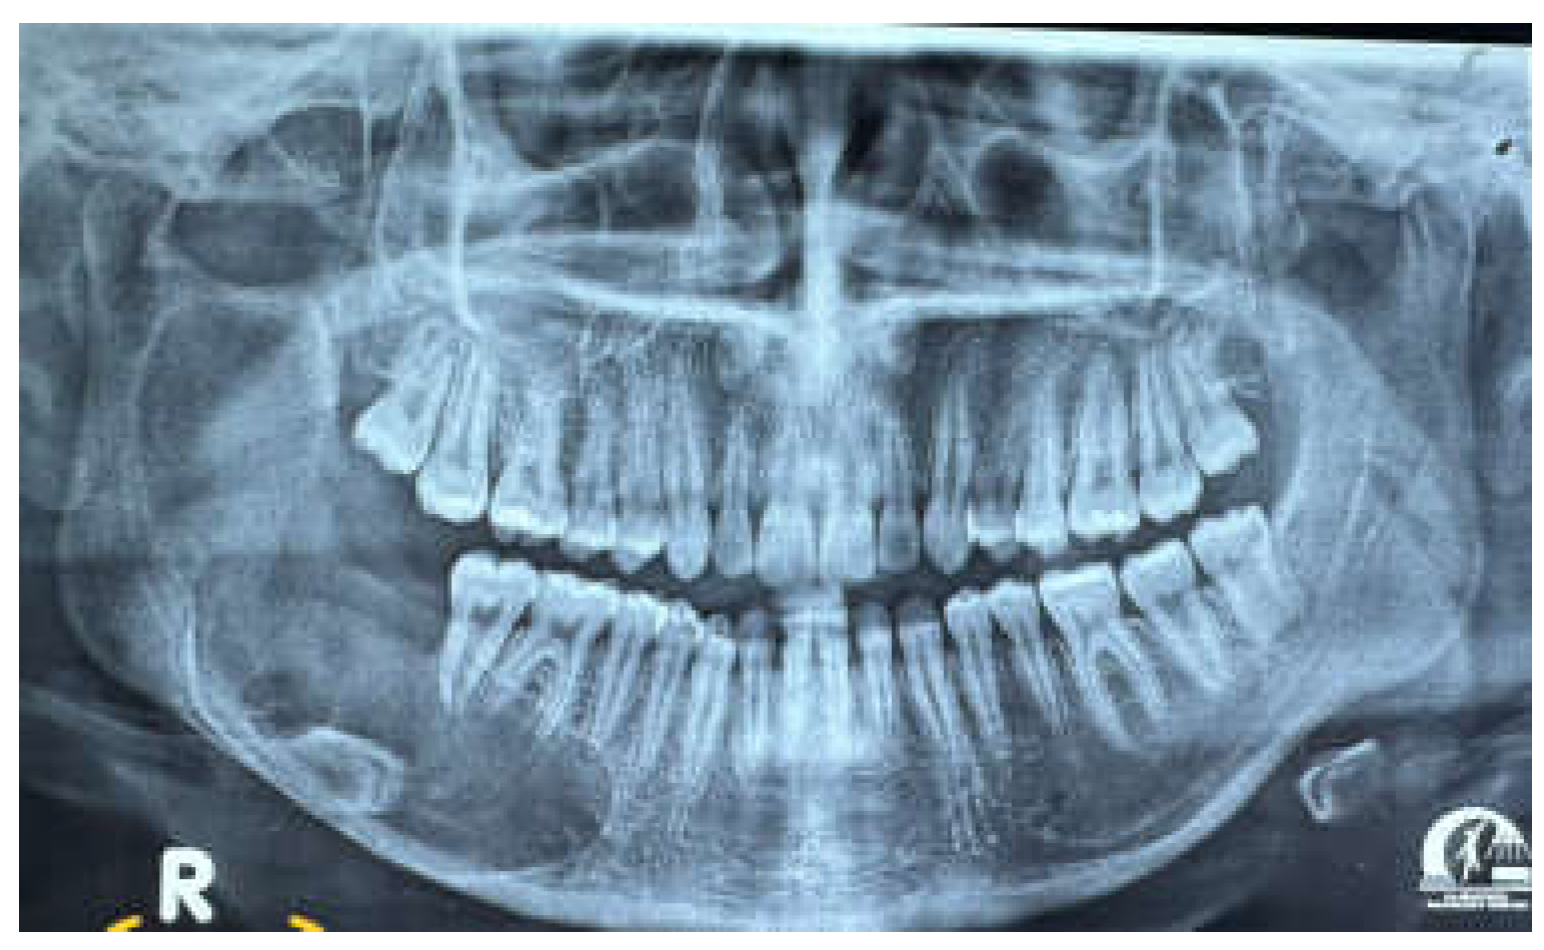

Figure 9. OPG showing 2 years postoperative.

An panoramic view was conducted 9 months after the excision, showing nearly complete mineralization of the osteolytic area. Additionally, there was significant ossification of the mandibular angle. The patient was monitored for 18 months following surgery. An panoramic view revealed complete healing of the lesion, full ossification of the defect, no signs of recurrence, and preservation of the mandibular angle and ramus profile. Clinically, the treatment resulted in no deformity, no changes to the mandibular contour, and no functional issues. The patient remained symptom-free and showed no significant neurological damage to the inferior alveolar nerve (IAN). However, due to the aggressive nature of this subtype of UA and the potential for recurrence, the patient will continue to be closely monitored with long-term clinical and radiological follow-up. This ongoing supervision will include periodic imaging studies to assess any potential changes in the mandibular area, ensuring early detection of any issues that may arise. Additionally, the healthcare team will provide the patient with guidance on maintaining optimal oral hygiene and overall health to support long-term outcomes.